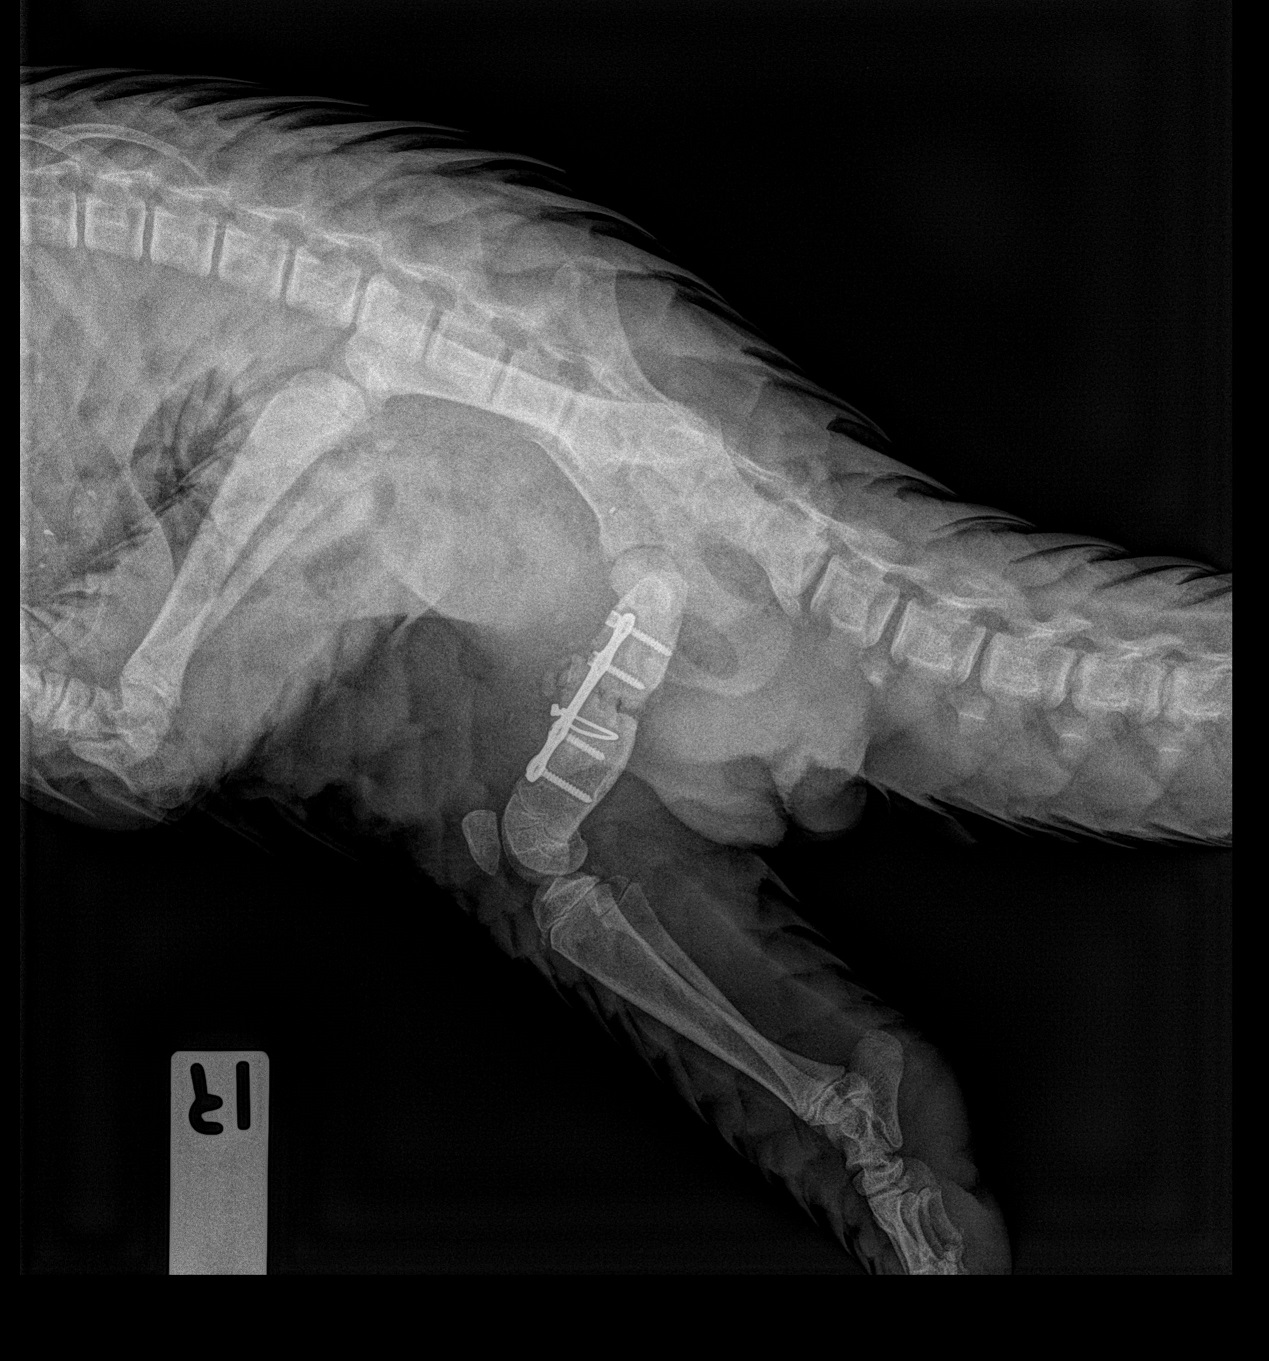

Close-up of Berani’s X-ray taken on 28 Jan 2019 showing that the implants are in place and that bone healing has been recorded.

Dr Charlene Yeong, Manager, Conservation & Wildlife Health, examines an X-ray of Berani’s right femur, and concludes that the implants are stable and bone healing has been recorded.